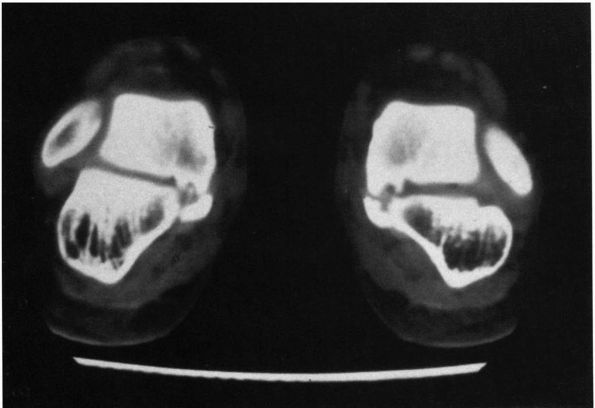

![]() |

FIGURE 20-18. Talocalcaneal coalition. Frontal section of a CT scan demonstrates tarsal coalition at middle facet joint.